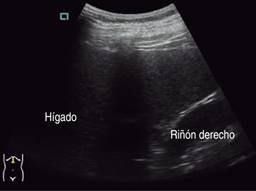

Ultrasonido de marzo reporta hígado de tamaño, forma y situación normales con borde inferior derecho irregular, de ecogenicidad heterogénea por presencia de una masa anecoica de forma redondeada y con bordes bien delimitados, paredes delgadas; sugestivo de quiste simple (Figuras 1 y 2).

Figura 1: Ultrasonido hepático con imagen anecoica redondeada y de paredes delgadas bien delimitadas.